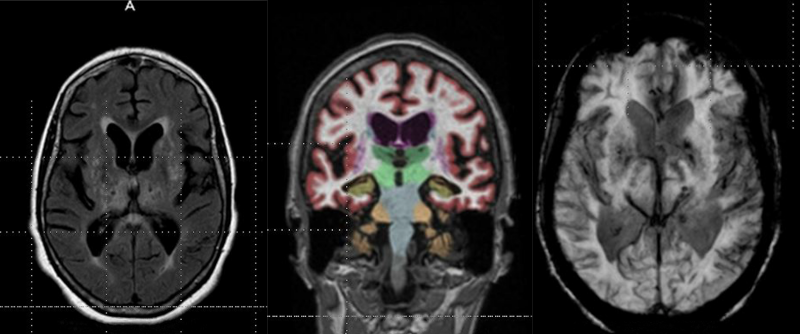

Philips announced that it has received 510(k) clearance from the U.S. Food and Drug Administration (FDA) for its Ingenia Elition 3.0T magnetic resonance imaging (MRI) solution and two clinical applications, Philips Compressed Sense and 3D APT. This integrated suite of innovations enables clinicians to perform exams up to 50 percent faster [1], increase diagnostic confidence and improve the patient experience.

Fujifilm’s APERTO Lucent is a 0.4T mid-field, open MRI system addressing today’s capability and image quality needs ...